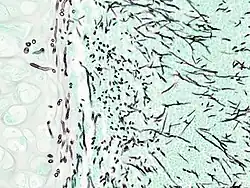

Angioinvasive pulmonary aspergillosis

-

Angioinvasive pulmonary aspergillosis (closeup)

On microscopy, Aspergillus species are reliably demonstrated by silver stains, e.g., Gridley stain or Gomori methenamine-silver.[27] These give the fungal walls a gray-black colour. The hyphae of Aspergillus species range in diameter from 2.5 to 4.5 μm. They have septate hyphae,[28] but these are not always apparent, and in such cases they may be mistaken for Zygomycota.[27] Aspergillus hyphae tend to have dichotomous branching that is progressive and primarily at acute angles of around 45°.[27]